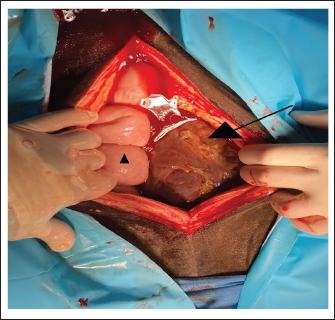

Immediately after a 30 cm long ventral midline incision, the GCT was visible in the surgical field (Fig. 3). It extended across the abdomen from the right to the left side. On the right side, it was adjacent to the caecum and the ascending colon, and the small intestine was visible underneath the GCT. Cranially, the GCT extended to the stomach and the caudal part of the lateral right lobe of the liver. Following the caudal surface of the GCT, the association of the GCT with the right ovary was ascertained. The right uterine horn and oviduct were palpable. Exteriorization of any part of the intestine was not possible due to the dimension and weight of the GCT. The ovarian pedicle and the uterus horn were also positioned underneath the GCT and could not be exteriorized. Due to the size of the mass, the only way to exteriorize the GCT and to ligate blood vessels was after its dissection into smaller segments. For the procedure, a tenotomy knife was used to transect the GCT in its length and approximately 1/3 of the mass was removed. Dissection of the GCT was performed blindly under manual control. The partial resection of the GCT was started in the ventral part of the GCT, which was visible after the ventral midline incision. Following the structure of the GCT, the dissection was continued dorsally, in the sagittal plane of the GCT. During the dissection, the bowel was protected under the hand of the surgeon performing the dissection, and an assistant provided support by removing the bowel from the incision line. The consistency of the GCT was firm and hard. The last centimeter of the dissected GCT, which was still connected to the main GCT, was bluntly separated by hand to avoid damage to the organs by the tenotomy knife.

Fig. 3. Surgical view following ventral midline laparotomy with the horse in dorsal recumbency. Cranial is at the bottom of the image. The GCT is seen against the abdominal wall (arrow). A small segment of the small intestine was visible (triangle). The dimension of the tumor did not allow any exteriorization from the large or small intestine and any manipulation was possible.